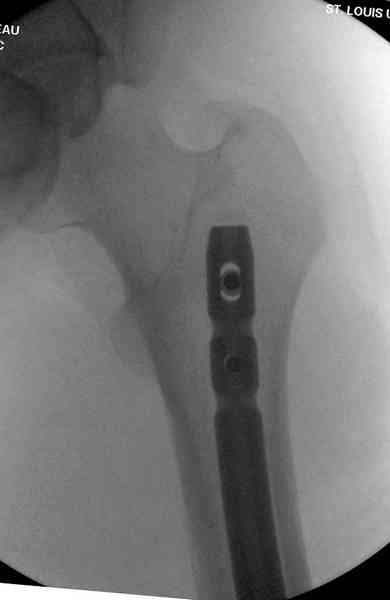

Пострадавшему 21 г., травма скоростная, после I&D с расширением раны, на бедре сделана операция ретроградным интрамедуллярным штифтом, остеосинтез с частичной резекцией надколенника и ушивание собственной связки.

На голень наружный фиксатор, рану на бедре ушили (рана была изнутри кнаружи всего 2 см). По протоколу травматических больных, до операции обследован ангиографически, (у больного дистально не смогли определить пульсацию) сосудистый хирург подтвердил проходимость на всем протяжении магистрального сосуда нижней конечности по снимкам ангиограмм.

В настоящее время больной в реанимации по поводу Черепно Мозговой Травмы и состояние улучшается. Запланировал ушивание раны в пятницу, если позволит состояние мягких тканей и при отсутстви отека возможно удастся просунуть перкутанномедиальную пластину.